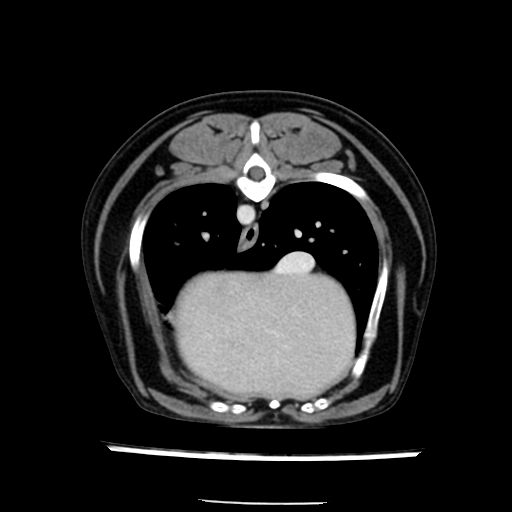

prescritto esame TAC

sequenza immagini limitata al fegato reni e surreni

le immagini ecografiche rispetto alla tac datano circa 7 mesi prima ,le surrenali sono normali nonostante il test acth sia risultato positivo .all’esame TAC dopo diversi mesi risultano aumentate armonicamente nel volume e si individua un forte sospetto di adenoma ipofisario .

sospetto adenoma ipofisario vs. meno probabilmente meningioma della base; intertiziopatia polmonare; lesione espansiva epatica, verosimilmente del lobo laterale sinistro, di sospetta natura neoplastica; lesioni spleniche di natura da definire; iperplasia/ipertrofia delle ghiandole surrenali, bilateralmente; vertebra di transizione del rachide toracico; tenosinovite cronica del muscolo bicipite brachiale di destra.